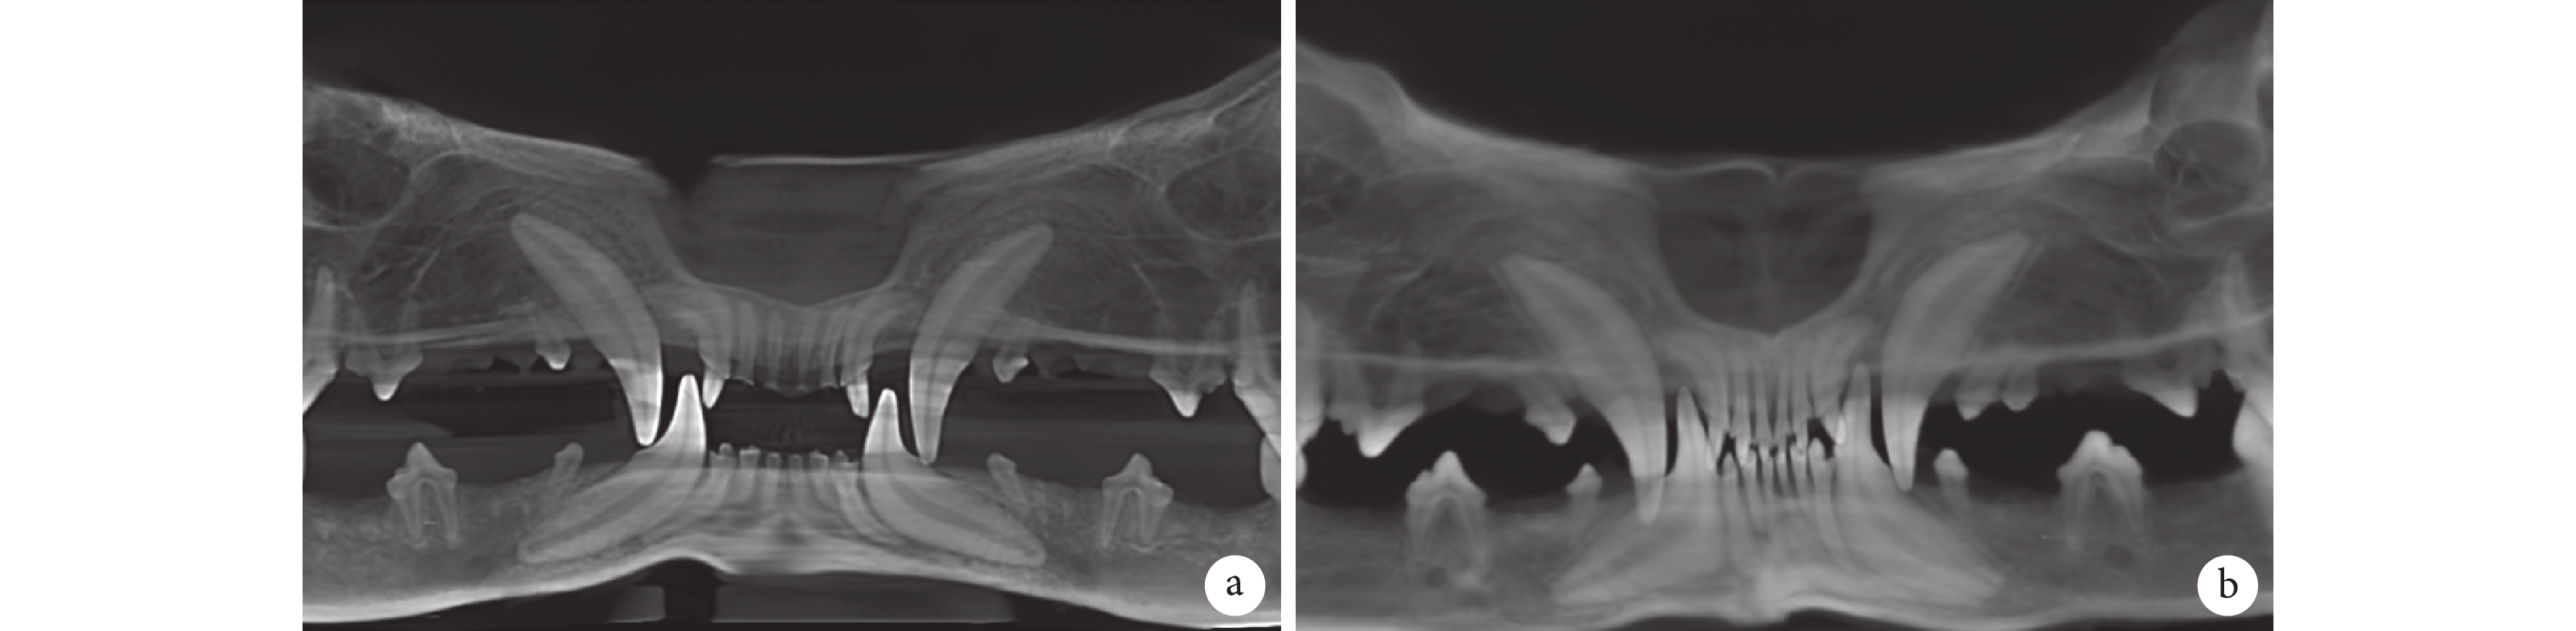

術后 1 個月,兩組植骨區均可見植骨材料殘留。術后 6 個月,兩組植骨區未見明顯植骨材料殘留,植骨區牙槽嵴高度均未見明顯降低,實驗組和對照組牙槽窩內骨量無明顯差異。見圖 4。術后 1、6 個月實驗組植骨處與對應參照區的灰度比分別為 0.97±0.14、0.93±0.06,對照組分別為 0.99±0.16、0.94±0.05,兩組比較差異均無統計學意義(t=?1.030,P=0.333;t=?0.770,P=0.466)。

a. 術后 1 個月;b. 術后 6 個月

Figure4. CBCT three-dimensional reconstruction after operationa. At 1 month after operation; b. At 6 months after operation